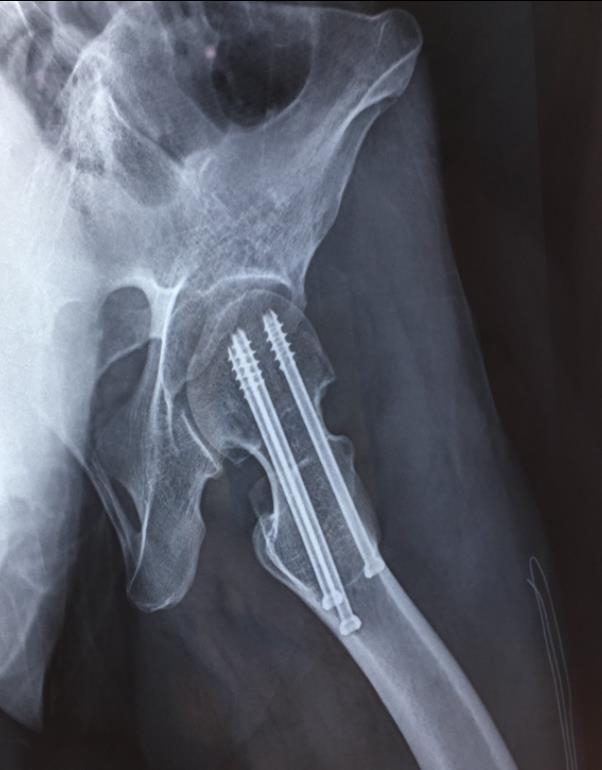

闭合复位经皮固定手术步骤

1、经皮沿股骨颈轴线置入空心钉导针,确保导针平行;

2、标准放置螺钉为倒三角形,其中下方螺钉在股骨矩,后方螺钉在后方骨皮质、研究发现倒三角形平行三枚螺钉能提供最佳的固定强度;

3、螺钉位于股骨颈四周,特别是后侧及下方,避免低于小转子方向进针,可能导致术后转子下骨折;

4、两个平面透视导针位置良好后切开皮肤,空心钻铭孔,导针引导下拧入空心钉,空心钉确保所有螺纹位于骨折线近端,螺钉头应距离软骨下骨5mm。

空心钉固定的三原则:“贴边、平行、倒品”

1、贴边是指3枚螺钉在股骨颈内,尽量靠近外围皮质。这样3枚螺钉作为一个整体,对整个骨折面可形成面状加压,如果3枚螺钉不够离散,更趋于点状加压,稳定性较差,不能较好地对抗扭转和剪切。

有研究显示,在侧位片上,螺钉的前后分布越分散,骨折不愈合发生率越低。J Bone Joint Surg Br. 2005 May: 87(5): 632-4.

图1 3枚螺钉在股骨颈内的理想位置

3、平行生物力学更稳定。